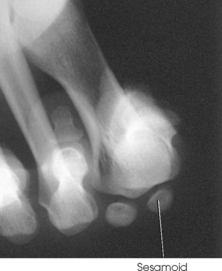

Beneath the head of the first metatarsal are two small bones called sesamoid bones. They are detached from the foot and embedded within two tendons. These bones are seen on most adult foot radiographs. They are a common site of fractures and must be shown radiographically (see Fig. 6-2).

Structures shown: The resulting image shows a tangential projection of the metatarsal head in profile and the sesamoids (Fig. 6-35).